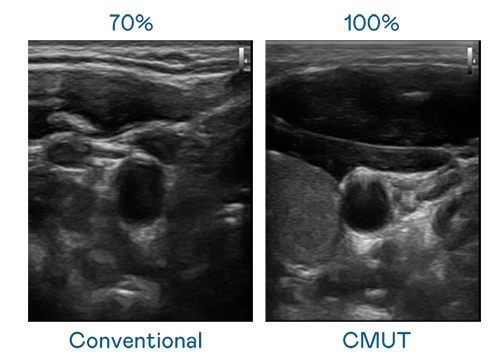

CMUT 技术是一种用电容式微机电元件来产生超音波讯号的技术。与传统 PZT 压电式技术相比,CMUT 频宽增加 30%,更宽频的超音波讯号让影像解析度大幅提升,是实现高影像品质医疗超音波扫描、促进精准医疗发展的关键技术。

大频宽带来超清晰影像

超音波影像的解析度高低,首先取决于探头能发出的讯号频宽。SG胜游 CMUT 可提供高清晰的超音波讯号,提供高频宽、高灵敏度、影像纹理细节更高的超音波影像,协助医护人员缩短影像判读时间及利用精准的医疗影像进行诊断。